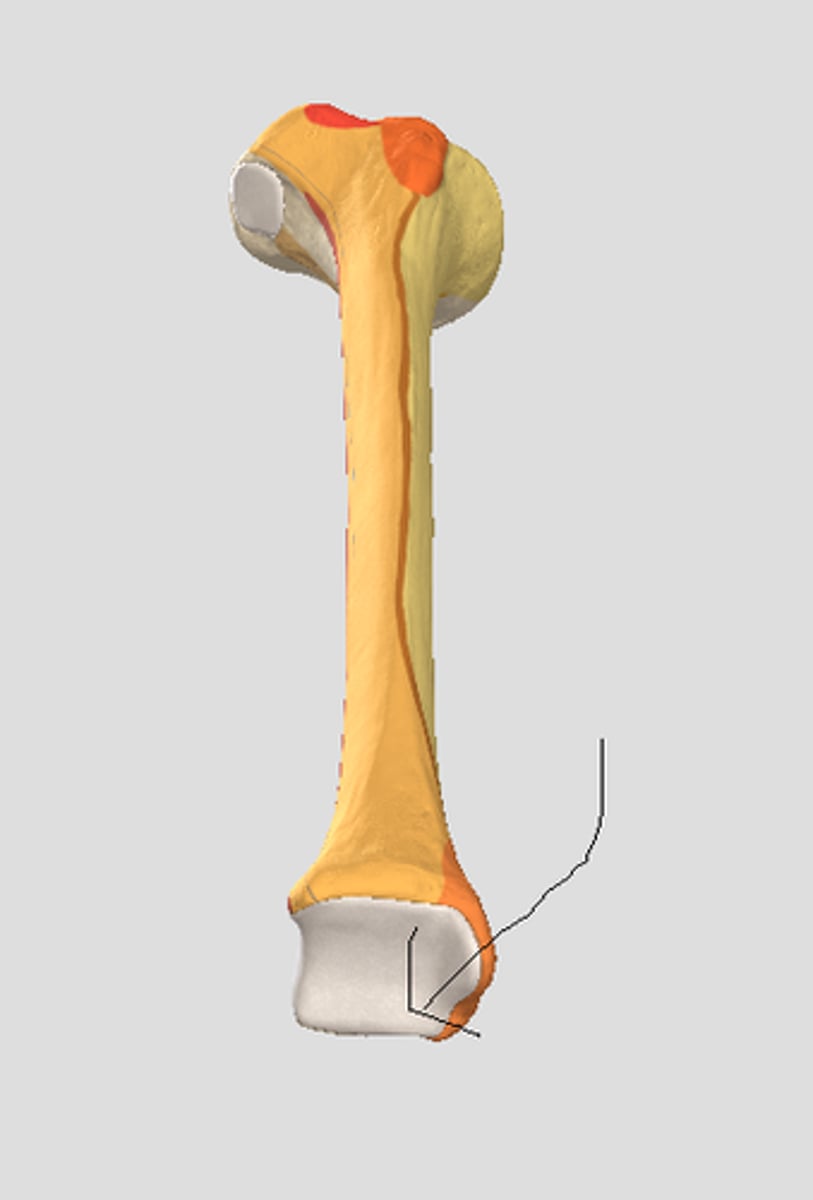

Quadriceps tendon

Patellar ligament